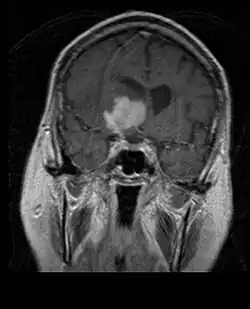

La tomodensitométrie (TDM) et L'imagerie par résonance magnétique (IRM) peuvent détecter efficacement une néoplasie dans le cerveau. L'IRM est plus sensible que la TDM pour identifier les lésions, mais présente des contre- indications pour les patients porteurs de stimulateurs cardiaques, de prothèses incompatibles, de clips métalliques et contre-indications. La TDM reste la méthode de choix pour détecter les calcifications au sein des lésions ou les érosions osseuses de la calotte ou de base du crâne. L'utilisation d' agents de contraste, iodés dans le cas du scanner et paramagnétiques (gadolinium) dans le cas de l'IRM, permet l'acquisition d'informations sur la vascularisation et l'intégrité de la barrière hémato-encéphalique, une meilleure définition de la tumeur tumorale par rapport à l' œdème environnant et à la génération d' hypothèses sur le degré de malignité. L'examen radiologique permet également d'évaluer les effets mécaniques et les modifications importantes des structures cérébrales résultant de la tumeur, telles que l' hydrocéphalie et les hernies, dont les effets peuvent être fatals. Enfin, en préparation à la chirurgie, ce diagnostic peut être utilisé pour déterminer la localisation de la lésion ou l'infiltration de la tumeur dans des zones vitales du cerveau. À cette fin, l'IRM est plus efficace que la tomodensitométrie car elle peut fournir des images en trois dimensions.

Sur-L'IRM montre une tumeur intracrânienne comme une lésion massive qui peut devenir plus luminescente après utilisation du produit de contraste. Cependant, il y a toujours une anomalie de signal dans -L'imagerie par résonance magnétique, qui indique la présence d'une néoplasie ou d'un œdème vasogénique. Habituellement, une luminescence accrue (amélioration du contraste) indique une tumeur d'un grade supérieur de malignité. Un anneau de contraste est caractéristique du glioblastome, avec la partie luminescente correspondant à la partie vitale de la tumeur maligne, et la plus foncée - zone hypointense correspondant à une nécrose tissulaire.

En règle générale, les patients atteints d'astrocytome anaplasique présentent des crises d'épilepsie, des déficits neurologiques focaux, des maux de tête et des changements de personnalité. L'âge moyen des patients est de 45 ans. L'imagerie par résonance magnétique montre généralement une lésion massive avec un signal de contraste accru, qui peut aussi être plus faible. Le diagnostic repose sur l'examen histologique de la lésion par biopsie ou résection chirurgicale.

L'IRM montre généralement une lésion de contraste massive impliquant le cervelet. Comme mentionné ci-dessus, le médulloblastome a une forte propension à infiltrer localement les leptoméninges ainsi qu'à se propager à travers l'espace sous-arachnoïdien, impliquant les ventricules, la convexité cérébrale et les surfaces leptoméningées de la colonne vertébrale. Par conséquent, il est nécessaire de mettre en résonance tout l'axe crânio-spinal.

Les patients atteints de méningiome peuvent présenter des symptômes typiques d'une lésion crânienne massive, notamment des convulsions et des déficits neurologiques focaux. détecté sur la tomodensitométrie et l'imagerie par résonance magnétique pour d'autres raisons. Cette tumeur de résonance a un aspect caractéristique, consistant généralement en un rehaussement de contraste uniforme le long de la dure-mère avec une séparation nette du parenchyme cérébral. Une autre caractéristique, bien que non présente dans tous les cas, est la soi-disant "queue durale", représentée par un renflement qui s'étend au-delà de la lésion et indique le point d'ancrage dans la dure-mère.

Les patients souffrent d'une variété de symptômes caractéristiques d'une lésion massive focale ou multifocale. L'IRM montre généralement des tumeurs avec un rehaussement de contraste homogène au sein de la substance blanche périventriculaire profonde. La multifocalité et le rehaussement inhomogène sont typiques des patients dont le système immunitaire est affaibli. L'analyse du lymphome du SNC est extrêmement importante dans le diagnostic différentiel de la néoplasie cérébrale. Il est à noter que l'administration de corticoïdes peut entraîner la disparition complète du rehaussement, rendant difficile le diagnostic des lésions. Par conséquent, si un lymphome du SNC doit être pris en compte dans le diagnostic différentiel, les corticoïdes doivent être évités à moins que l'effet de masse ne provoque un problème grave et immédiat chez le patient.